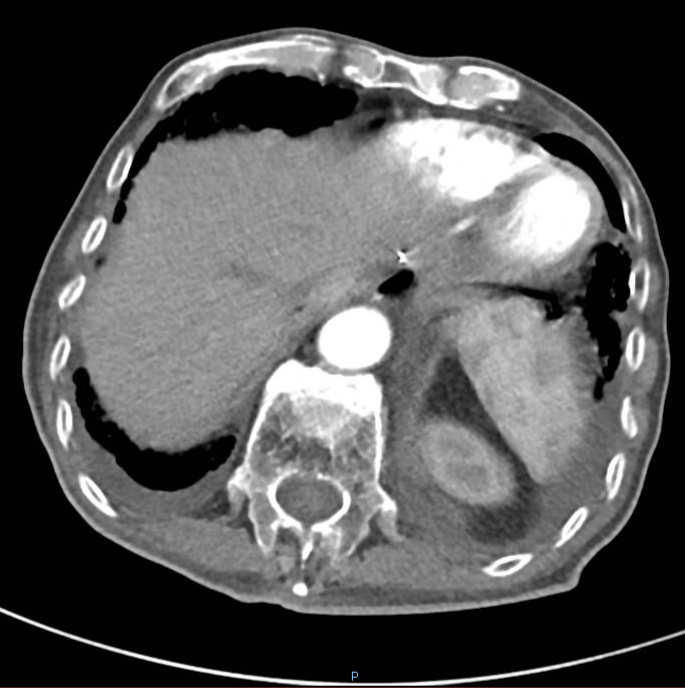

2020-01-08复查腹部CT:与患者前片(2019-7-8)比较显示:食管胃吻合口区低密度病变范围较前缩小。所示腹部其余病变较前未见明显变化,双肺片状高密度影,双侧胸腔积液。

△2020.01腹部CT

2020-08-31复查腹部CT:与患者前片(2020-1-8)比较显示:所示腹部病变较前未见明显变化。双肺高密度影范围较前缩小。

△ 腹部CT 2020.08